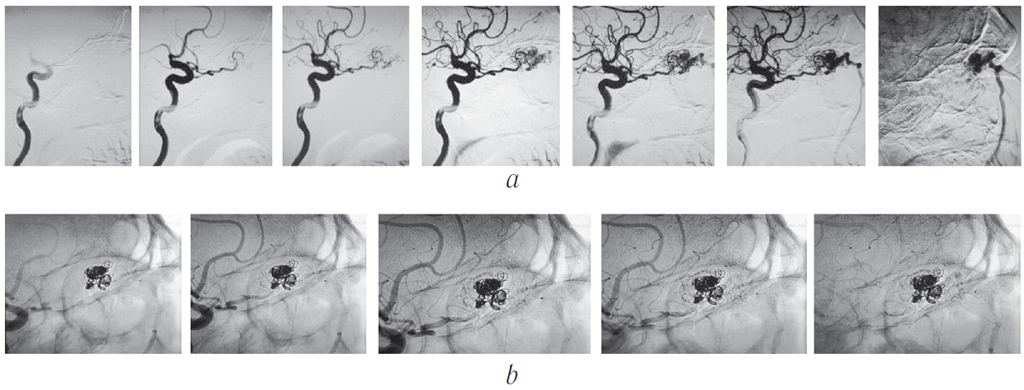

Катетеризирована правая внутренняя сонная артерия. Выполнена стандартная и ротационная ангиография. При стандартной субтракционной (рис. 13) и ротационной (рис. 14) ангиографии визуализируется выраженная собственная сосудистая сеть новообразования правой орбиты, источником которой является правая глазная артерия. Венозный отток осуществляется по варикозно расширенной дренирующей угловой вене, впадающей в лицевую вену.

Рис. 13. Субтракционная ангиограмма в боковой проекции: а — артериальная фаза; b — венозная фаза. 1 — правая внутренняя сонная артерия; 2 — глазная артерия; 3 — собственная сосудистая сеть новообразования; 4 — варикозно расширенное устье дренирующей вены; 5 — дренирующая лицевая вена

Fig. 13. Subtraction angiogram in lateral projection: а – arterial phase, b – venous phase. 1 – right internal carotid artery; 2 – ophthalmic artery; 3 – own vascular network of the neoplasm; 4 – varicose dilated drainage vein opening; 5 – draining facial vein

Рис. 14. Ротационная ангиограмма: a — общий вид в боковой проекции; b — вид сосудистой сети новообразования слева; c — вид сосудистой сети новообразования справа. 1 — глазная артерия; 2 — центральная артерия сетчатки; 3 — собственно сосудистая сеть новообразования; 4 — дренирующая вена; 5 — афференты сосудистой сети; 6 — варикозно расширенное устье дренирующей вены; 7 — артериовенозные фистулы (шунты)

Fig. 14. Rotational angiogram: a – general appearance in lateral view; b – left-side appearance of vascular network of the tumor; c – right-side appearance of vascular network of the tumor. 1 – ophthalmic artery, 2 – central retinal artery, 3 – proper vascular network of the neoplasm, 4 – draining vein, 5 – vascular network afferents, 6 – varicose dilated drainage vein opening, 7 – arteriovenous fistulas (shunts)

Для достижения радикальности эмболизации, прекращения потока по дренирующей вене через микрокатетер введена жидкая клеевая композиция ONYX18. При контрольной ангиографии контрастирования сосудистой сети опухоли не наблюдалось (рис. 15).

Рис. 15. Динамика эмболизации сосудистой сети опухоли отделяемыми микроспиралями и результаты ангиографии: а и b — динамика эмболизации сосудистой сети опухоли; с — этапная ангиография через трансвенозный микрокатетер; d — конечный результат после введения жидкой неадгезивной клеевой композиции ONYX18; е — контрольная ангиография, конечный результат — собственная сосудистая сеть не контрастируется, дренирующая вена не заполняется. 1 — клубок микроспиралей Target, 2 — метки микрокатетеров, 3 — замедление кровотока по дренирующей вене, 4 — жидкая неадгезивная клеевая композиция в дренирующей вене, 5 — глазная артерия

Fig. 15. Dynamics of tumor vascular network embolization by detachable microspirals, and the results of angiography: a and b – dynamics of embolization of the vascular network of the tumor; c – phased angiography through a transvenous microcatheter; d – final result after the injection of the liquid non-adhesive composition ONYX18; e – control angiography, the final result – proper vascular network is not contrasted, the draining vein is not filled. 1 – Target coils, 2 – microcatheter tags, 3 – slowed blood flow through the draining vein, 4 – liquid non-adhesive composition ONYX18 in the draining vein, 5 – ophthalmic artery

При контрольной ангиографии (рис. 16, 17, b) отмечено отсутствие контраста в сосудистой сети опухоли с выраженным замедлением тока крови по дренирующей вене и приводящей ветви глазной артерии. Церебральные ветви проходимы, диаметр и топография их сохранены.

Рис. 16. Контрольная ангиограмма правой внутренней сонной артерии и сосудов правой глазницы, сагиттальная проекция: артериальная (а) и венозная (b) фазы. В артериальную стадию (a) контрастируется глазная артерия (2), сосудистая сеть новообразования не определяется. В полости образования в обе стадии ангиографии (a и b) визуализируются рентгеноконтрастные эмболизирующие микроспирали (5). В венозную стадию (b) отток из опухоли в правую лицевую вену отсутствует (4)

Fig. 16. Control angiography of the right internal carotid artery and vessels of the right orbit, sagittal projection: arterial phase (a) and venous phase (b). At the arterial phase (a), the ophthalmic artery is contrasted (2), the vascular network of the neoplasm is not detected. In the cavity of the tumor in both stages of angiography (a and b), radio opaque embolizing microspirals (5) are visualized. At the venous phase (b), there is no outflow from the tumor into the right facial vein (4)

Рис. 17. Динамика заполнения сосудистой сети новообразования глазницы контрастом по результатам ангиографии: а — до эмболизации: постепенное заполнение артериальной сети церебральных сосудов, а затем и сосудов опухоли с переходом в венозную фазу; b — после эмболизации

Fig. 17. Dynamics of filling of the vascular network of the orbital neoplasm with contrast according to the results of angiography: a – before embolization: gradual filling of the arterial network of the cerebral vessels and then those of the tumor with the transition to the venous phase; b – after embolization

Поэтапная динамика заполнения церебральных сосудов и сосудистой сети новообразования глазницы контрастом в ходе ангиографии до и после эмболизации сосудов новообразования показана на рис. 17.